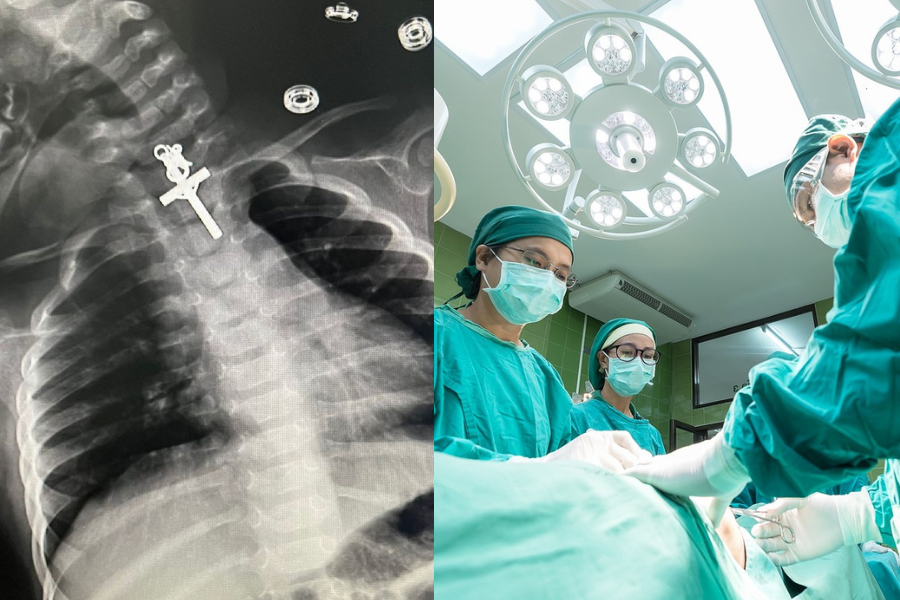

Médicos sacaron un crucifijo del esófago de una lactante: “Dios nos ha dado una oportunidad de vida"

La menor fue sometida a una endoscopía terapéutica, luego que el examen de tórax revelara que tenía un extraño objeto en su interior.

Médicos de Perú debieron realizar una delicada intervención tras notar que una guagua de diez meses tenía un crucifijo en el esófago. Esto luego que la madre, Mari Carmen Sejami Rosas, llevara a la bebé a urgencias del Hospital Víctor Lazarte Echegaray en la ciudad de Trujillo, debido al llanto permanente de la menor. Según lo informado por Andina, la lactante fue sometida a un examen de tórax que mostró que tenía un crucifijo de metal en el esófago. Lo anterior llevó a los cirujanos del servicio de gastroenterología a realizar una endoscopía terapéutica que permitió extraer el objeto con éxito. “Tuvimos que esperar seis horas para que el estómago se vaciara, ya que había tomado su leche. Luego de eso, se procedió con la compleja intervención y todo salió muy bien”, explicó el médico Luis Alberto Esteves. Por su parte, la mujer agradeció el trabajo del equipo médico, puesto que temió que se produjera un desenlace fatal.  “Estoy muy agradecida. Dios nos ha dado una oportunidad de vida y agradezco a los doctores por su excelente labor”, dijo Mari Carmen.